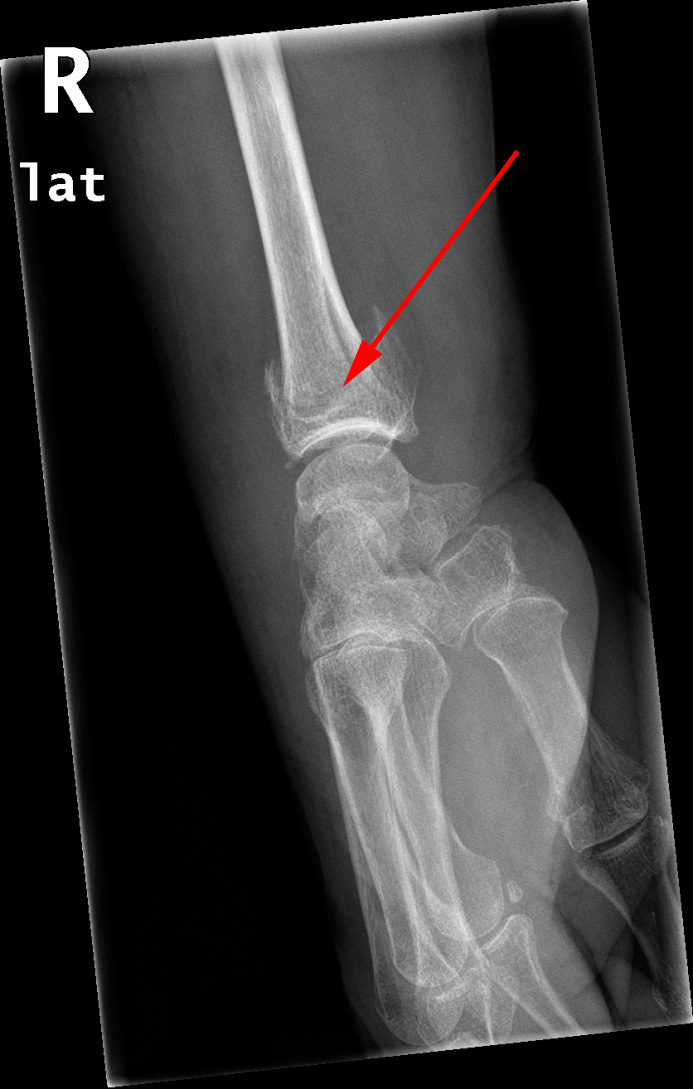

Røntgenundersøgelse af hånden viser distal radius fraktur (røde pil)